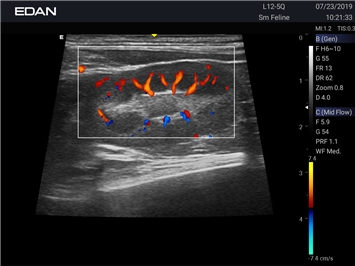

Ветеринарный ультразвук одним нажатием. Система Acclarix AX2 VET разработана с целью обеспечить бескомпромиссную производительность по доступной цене. Наличие уникальных двойных аккумуляторов в легком корпусе массой 4,5 кг из магниевого сплава позволяет системе Acclarix AX2 VET удовлетворять все потребности ветеринарных исследований, сохранив низкую стоимость.

EDAN Acclarix AX2 VET представляет собой специализированную ветеринарную ультразвуковую систему, сочетающую высокую производительность с доступной ценой. Благодаря продуманной конструкции и передовым технологиям, система обеспечивает качественную диагностику животных различных видов.

Цветовой допплер:

Да

Энергетический допплер: